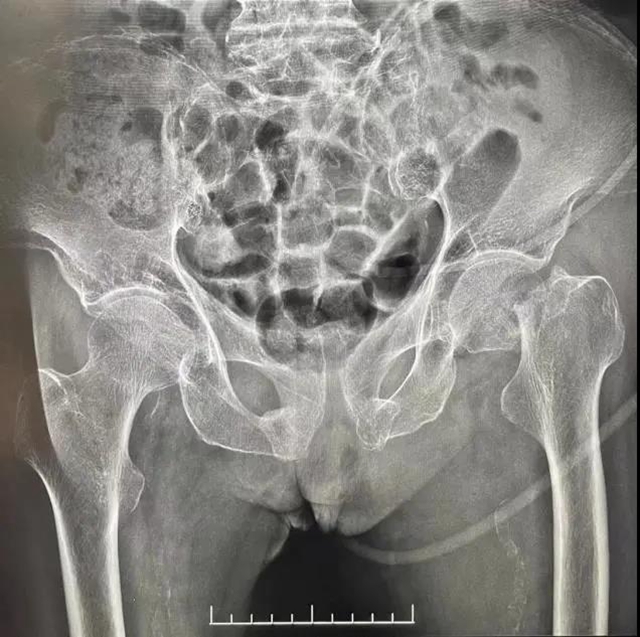

何婆婆今年已经94岁高龄,9月在家里行走时不慎滑倒,导致左侧髋部疼痛、活动受限,当地医院考虑到老人岁数大、风险高,建议选择保守治疗。但保守治疗患者只能长期卧床,最终可能“一睡不起”。患者家属四处咨询,最终到西南医科大学附属医院骨与关节外科谭...